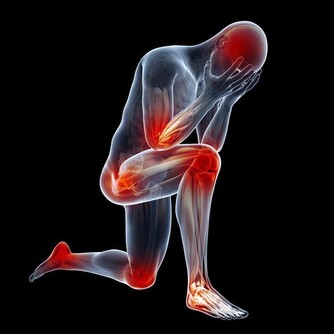

第三道坎:50~80歲:心髒病和腦卒中關

很多人的心腦等重要器官長年高負荷運轉,加上各種不良嗜好,平時又不注意保養,

血管在50歲左右已經逐漸硬化,血管壁上佈滿斑塊。

這個年齡段的人很容易患上腦梗塞、突發腦卒中、心肌梗死等急症。

警惕:一旦感覺到胸悶、氣短、前胸痛,或體力突然下降、極度乏力,千萬不要扛著,一定要提高警惕。